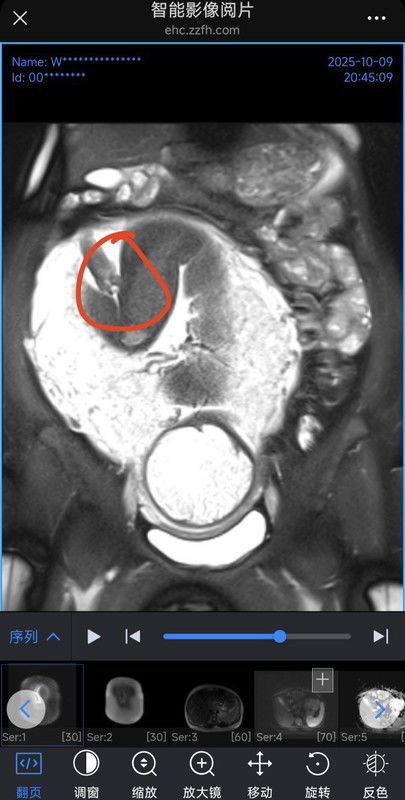

Check MRI saat janin 37W5D, benarkah itu testis Dan penis janin ya bun ? saya penasaran apa baby saya cow ? atau itu tali pusar(placenta) ya bun, itu posisi placenta Ada disamping tangan (bisa di check di photo2). Ada short video cuma gak bisa di upload disini 🙏🏻 #mohonbantujawabbunda ##Sharingdong_Bund #bantujawab #sharing #firstmom #AskingAsAMom #pregnancy